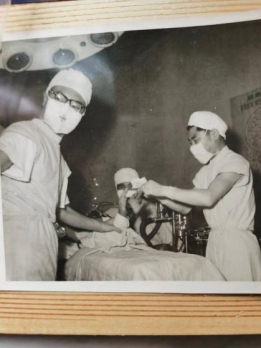

陈秉礼教授进行手术。院方供图

当时的骨科只有十几张病床,但慕名前来的患者却络绎不绝,陈秉礼主任有时一天都要做好几场手术,最长的一次显微外科断指再植手术竟然连续做了三十多个小时。虽然当时条件很艰苦,但老一辈骨科专家们却咬牙坚持,因为这是患者的信任与希望!